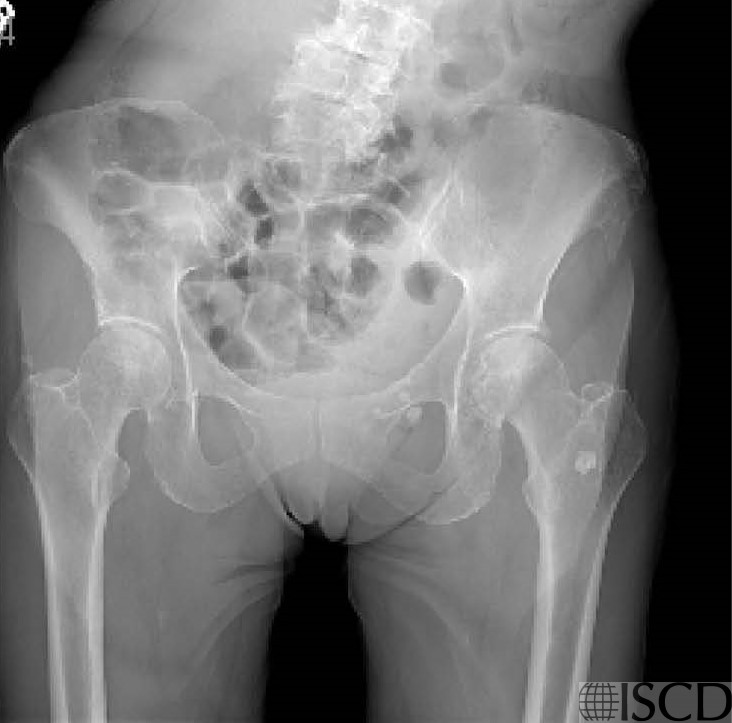

Calcifications in the Soft Tissue Projecting over the Left Hip

There are calcifications that project over the left intertrochanteric region of the hip on the Hologic left hip scan.

This plain radiograph also shows the calcifications. From other radiographs available, it was determined that the calcifications were in the soft tissue and projected over the hip.

There are well circumscribed dense calcifications which project over the intertrochanteric region of the left femur. From other imaging the patient available, it was included that these calcifications were in the soft tissue.